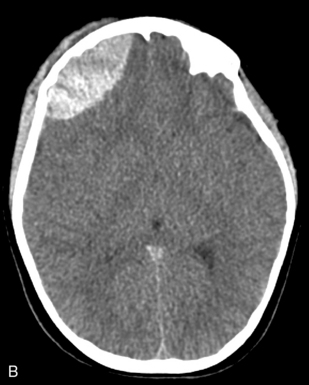

Tension pneumothorax develops from progressive air entry into the pleural space from the lung or airways; this air accumulation elevates intrapleural pressure, compresses the lung, and can compromise cardiovascular function. The lung on the side of the tension pneumothorax is partially collapsed, and severe hypoxemia develops (Fig. 19-3; see Fig. 10-7). Breath sounds and chest expansion on the side of the pneumothorax are decreased or absent.

image

Fig. 19-3 Chest radiograph showing tension pneumothorax. A, Right tension pneumothorax produces displacement of the mediastinum to the patient’s left side (arrow). Note the absence of rib fractures. This injury was sustained when the rear wheels of a car ran over the child’s right chest, and the tension pneumothorax was apparent on clinical examination. B, Reexpansion of the right lung is apparent after insertion of a chest tube. The mediastinum has shifted back to the midline. Opacification of the right lung is consistent with pulmonary contusion. The child is intubated and a nasogastric tube is in place. Note that the chest radiograph did not and should not delay thoracostomy.

(Chest radiographs courtesy of James Betts, Oakland, CA.)

A tension pneumothorax shifts the mediastinum away from the affected side. This shift reduces venous return to the heart and decreases cardiac output; neck vein distension may be observed. In addition, the point of maximal impulse and the trachea shift away from the tension pneumothorax,4 although the tracheal shift may be difficult to appreciate in infants and children. The resultant decrease in cardiac output and oxygen delivery are life threatening. The mediastinal shift can result in compression of the contralateral lung, further compromising oxygenation and ventilation.

A tension pneumothorax requires immediate needle decompression followed by tube thoracostomy. Needle decompression should be performed on the basis of clinical examination, and providers should not delay therapy to obtain a chest radiograph. A simple pneumothorax is treated with chest tube insertion.